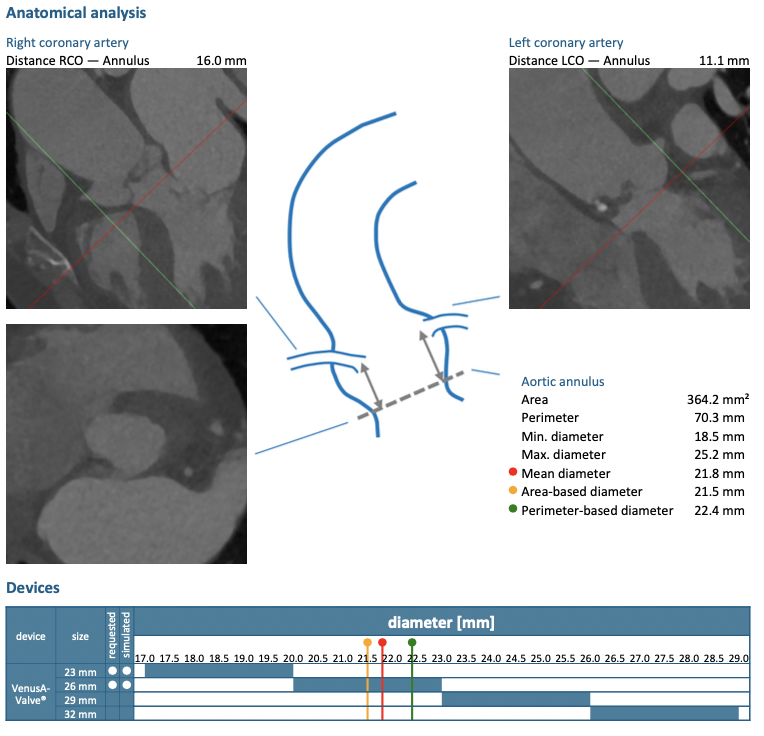

主动脉CT

难点分析:

*患者为TYPE1型二叶瓣,左右融合,重度钙化,融合脊难以推开,瓣膜释放后具有一定瓣周漏风险;

*心脏角度为60°,横位心,输送器过瓣难度增加,瓣膜植入同轴性差,瓣膜释放更易移位,增加了操作的难度;

*髂动脉走形迂曲,升主动脉明显扩张,术中操作需轻柔;

制定策略:

经分析研判,拟从右侧股动脉穿刺入路,使用23mm球囊预扩,采取downsize手术策略,选用L26号的VenusA-Valve瓣膜,因患者为横位心,瓣膜释放同轴性差,容易发生移位,故采用VenusA-Plus可回收输送系统确保瓣膜的稳定释放,瓣膜释放后结合造影和超声情况,决定是否后扩。